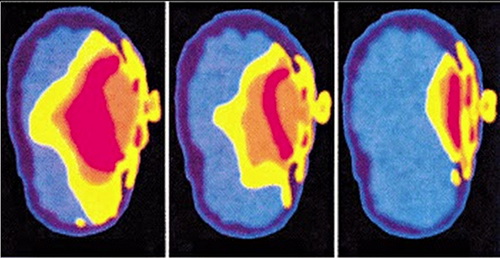

Một nhóm nhà khoa học cho rằng, trẻ em chịu ảnh hưởng bức xạ

sóng điện từ nhiều hơn so với người lớn. Ảnh: Collective-evolution.

Trang Collective-evolution nhấn mạnh thêm về tác động của bức xạ điện từ với não bộ của trẻ em do khả năng hấp thụ cao hơn nhiều so với người lớn. Tuy nhiên, các nhà khoa học cũng khuyến cáo các bậc phụ huynh không nên lo lắng quá. Trong khi chờ những kết luận khoa học cuối cùng, cha mẹ có thể thực hiện một số biện pháp bảo vệ.

Đừng để con nhỏ dùng điện thoại di động hay những thiết bị thu phát sóng không dây, trừ một số trường hợp khẩn cấp. Trẻ em dễ ảnh hưởng bởi bức xạ từ điện thoại do hộp sọ mỏng hơn so với người lớn. Ngay cả cha mẹ cũng nên hạn chế dùng thiết bị này.